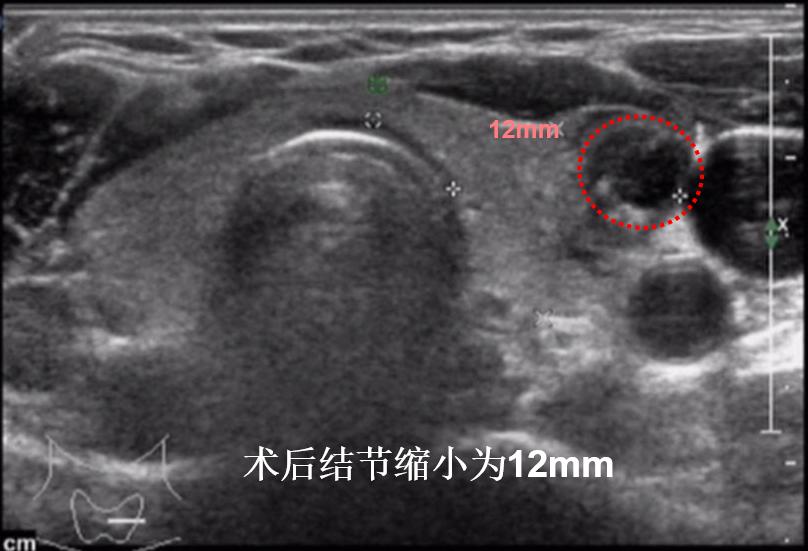

病例②:左侧颈部6cm巨大甲状腺结节,经微创消融后,肿物完全消失,颈部恢复正常外观

微创消融前后超声对比,体积缩小99%